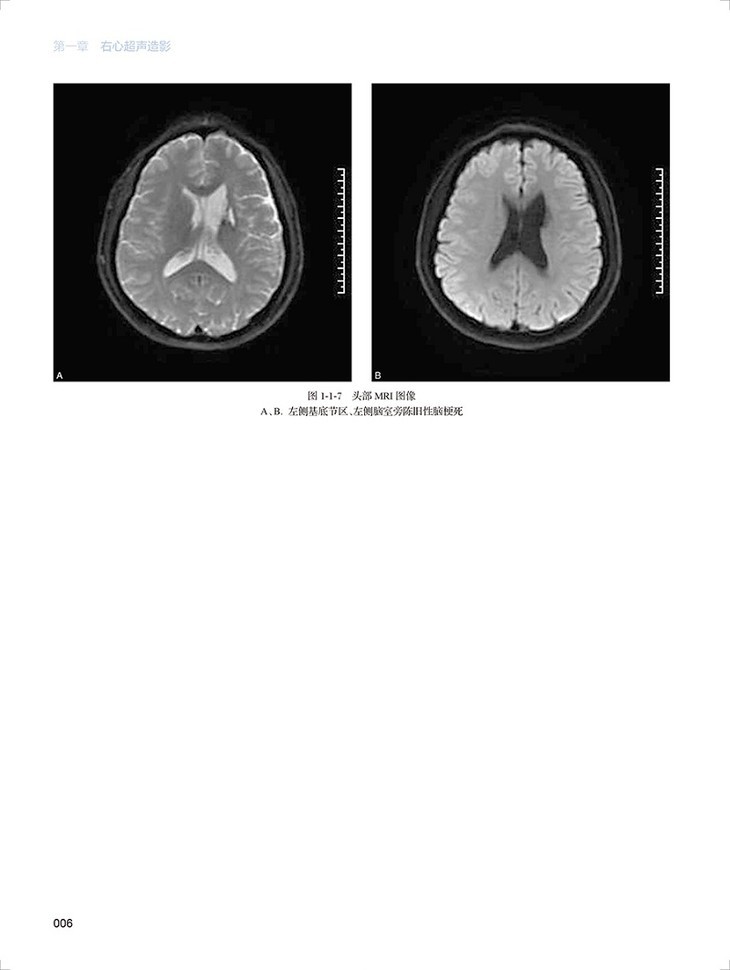

心血管超声造影图鉴共有文字内容60千字,图片454幅,视频212个。全书分为三章三十一节内容,分为左心超声造影、右心超声造影和血管造影三个板块,包括了卵圆孔未闭右向左分流、肺动静脉瘘、永存左上腔静脉、房间隔缺损封堵术后评估右向左的残余分流、部分型肺静脉异位引流、应激性心肌病、左心房黏液瘤、心腔内血栓等疾病的超声造影表现。每个病例分为病史概要、常规超声图像、超声造影图像、经食道超声心动图和超声造影要点五个小标题,内容精炼、脉络清晰、一目了然。各个病例配了多张彩图和视频进行对照,读者可以扫描图片右侧二维码观看视频,方便快捷。